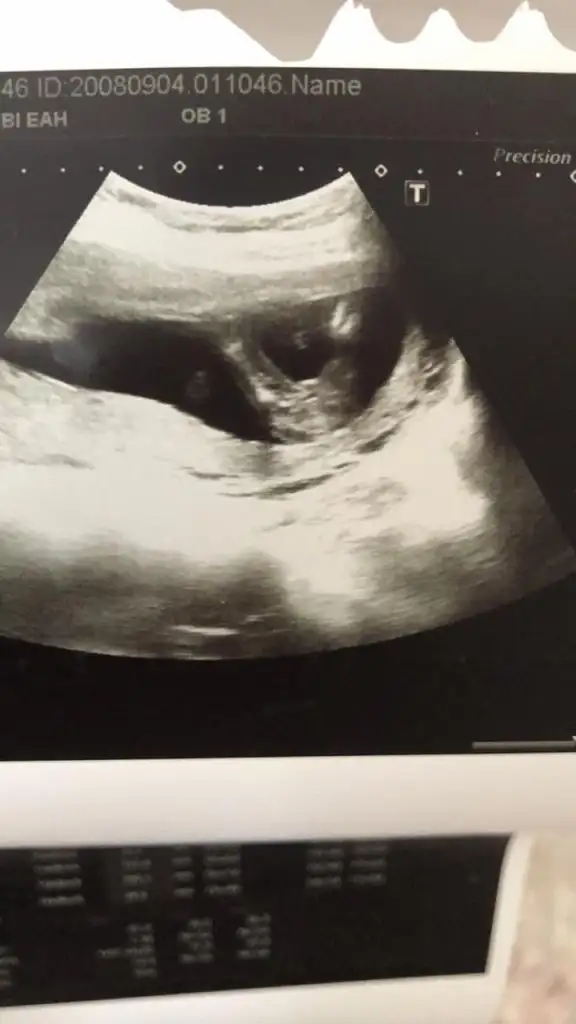

Bu bacak arası evet. Benim de ilk erkek olarak söylemişti doktorum sonra kız oldu. Hala tereddütteyim ben de. Detaylıya kadar bekliyoruz o yüzden :)Ya arkadaşlar bebeğim 16 haftalık bugün 4 lü tarama için gittim 16 hafta boyunca bebeğe erkek diyen doktor bugun de kıza benziyo dedi şaştım kaldım nasıl öğrencem ben cinsiyeti doğru hangisi ? EKLEDİĞİM GÖRSELDE BACAK ARASINI MI ÇEKTİ BİLMİYORUM BAKAR MISINIZ

Bebeği 16. Haftaya kadar böyle görerek söyledi dünde dörtlü taramada tek tek vücudunu ölçerken kız dedi ama erkek demiştiniz dedim bak çıkıntısı yok kıza benziyo yani dedi şaşırdı o da erkek mi demişim dedi16 haftaya kadar bacak arasını görerek mi çıkıntı var dedi? Yoksa yandan mı bakıyordu? Birde 16.haftada bacak arasına baktığında üç çizgiden bahsetti mi?

Ama bacak arasını net görmemiş demekki… keşke net görmüyorsa söylemeseler… yani benim 12 haftada bacak arası boştu ama yandan bakınca vardı çıkıntı… kızda da da erkekte de bu haftalarda olur çıkıntı oyüzden bacak arasını görmek lazım… instagramda mehmet boz’un videolarını bak cinsiyetle ilgili… aslında çok net oluyor her şey…Bebeği 16. Haftaya kadar böyle görerek söyledi dünde dörtlü taramada tek tek vücudunu ölçerken kız dedi ama erkek demiştiniz dedim bak çıkıntısı yok kıza benziyo yani dedi şaşırdı o da erkek mi demişim dedi

Ya bence ne biliyor musun… o bacak arası pozu yakalayamıyorlar ve tahmini olarak söylüyorlar… yani önce bacak arasını gör emin ol sonra konuş değil miBende bunu anlamıyorum 10 haftada cinsiyet görüyor ve gösterince de gerçekten mantıklı geliyor bide değiştiğini de pek sanmıyorum bizimkiler nasıl görmüyor bilmiyorumbiri de altına yazmıştı videoların 10. Haftada cinsiyeti gören koca yürekli doktor ve 16. Haftada hala cinsiyeti göremeyen benim doktorum diye